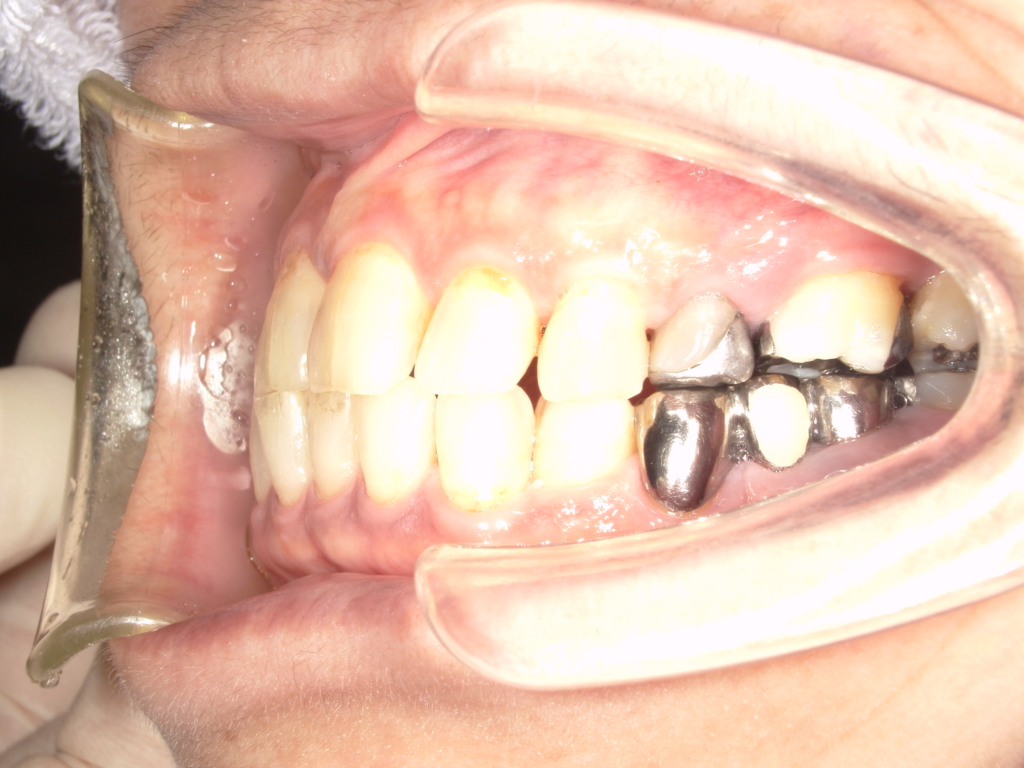

Y様インプラント実例 #44

左の上下の奥歯をインプラントで治療しています。

左下の奥歯は歯を抜くのと同時にインプラントの埋め込みを行っています。

被せものは上下、セラミックスで作っています。

治療前

治療後